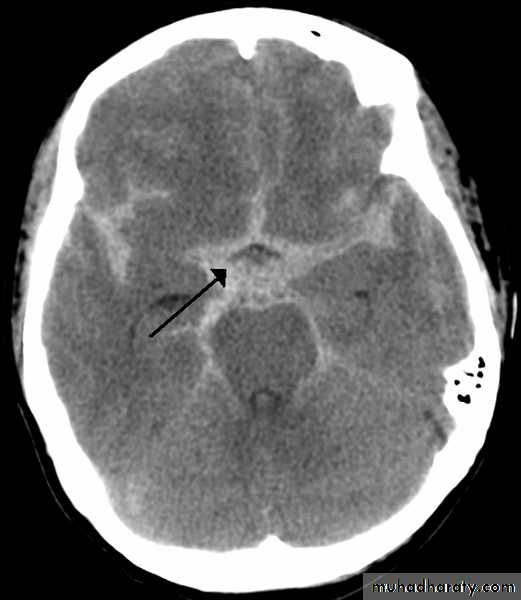

Subarachnoid hemorrhage

causesdue to ruptured aneurysm over 90 % of cases spcially at the circle of Willis .

ruptured AV malformation .

trauma .

CT finding

hyper density is seen within the SAS ( hyperdense sulci , being filled with clotted blood)

opacified inter hemispheric fissure ( become white & more dense )

opacification of the falx cerebri .

SAH

White sulciOpacified IHF